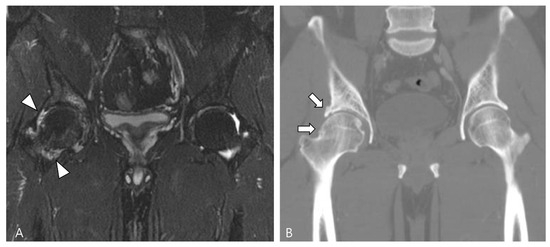

2.4. Relationship to Adjacent Structures of D-TSGCT

3.1. Differential Diagnoses of Intra-Articular D-TSGCT